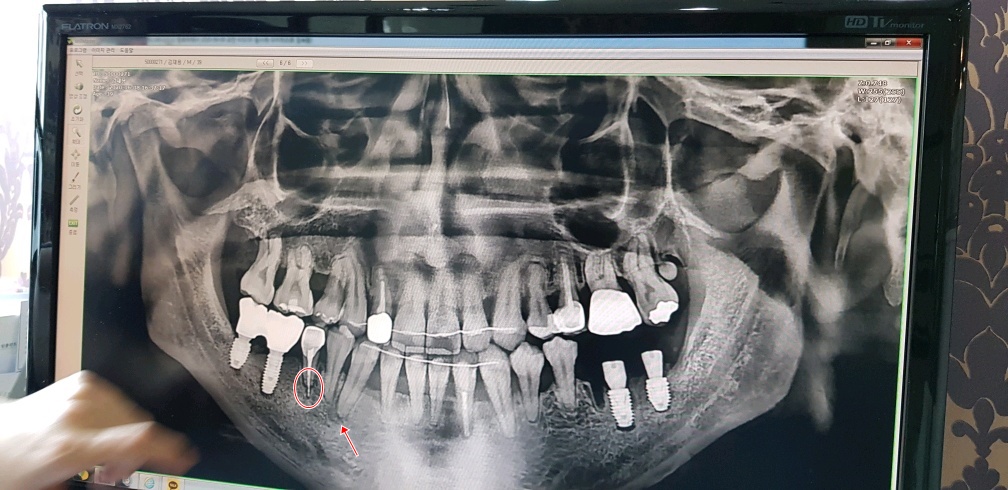

신경치료 하면서 심어놨던 하얀색(치아뿌리의 중간부분)이 치아뿌리 안쪽에만 있어야 되는데

뿌리를 넘어서서 아픈것일 수도 있다고 하고(실제로 살짝 딱딱한걸 깨물어 보면 통증이 장난아니다..)

두번째로는 화살표 표시해둔 부분 이부분이 치아뿌리 끝 부터 염증이 생겨서 아픈것 일수도 있다고 한다..

우선 임플란트수술 하고 집에 오긴 했으나 수술한 곳은 안아픈데 동그란표시해 둔 저 치아가 너무 아파서

몇시간 마다 진통제 없이는 못버틸 정도로 아프다...

저 치아도 뽑고 임플란트 해야된다는 건지.... 햐~ 참나..